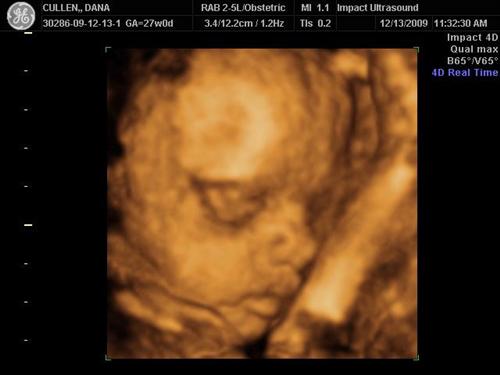

3d/4d sono

Last Update: 12/13/09